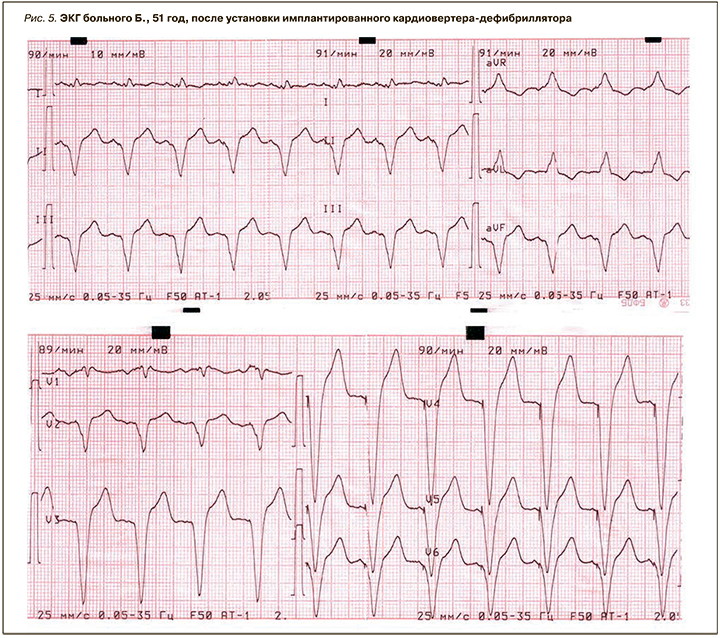

Пациенту установлен электрокардиостимулятор с частотной адаптацией (ЭКС DDDR) с функцией кардиовертера-дефибриллятора (ИКД) (рис. 5).

После установки ИКД состояние пациента существенно улучшилось: ЧСС увеличилась до 60–84 в мин, повысилась толерантность к физической нагрузке, головокружение не беспокоило.